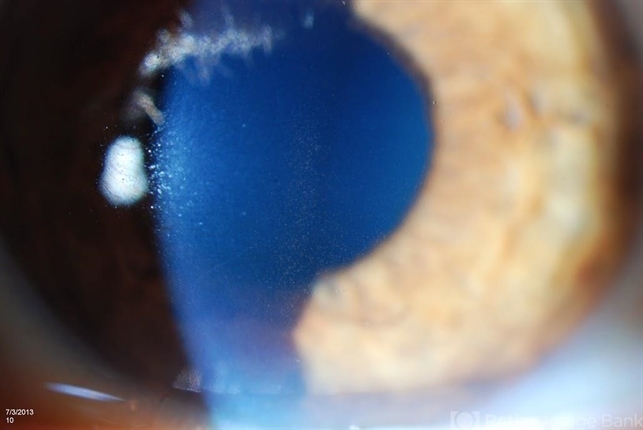

- Krukenbergs Spindle

- Krukenberg's spindle

- Jason S. Calhoun, Department of Ophthalmology, Mayo Clinic Jacksonville, Florida

Photo slit lamp biomicroscope

TOPCON D-90 SL NIKON CAMERA - Description

- Slit lamp shows pigment on the lower quadrant of the endothelium due to pigment dispersion glaucoma.